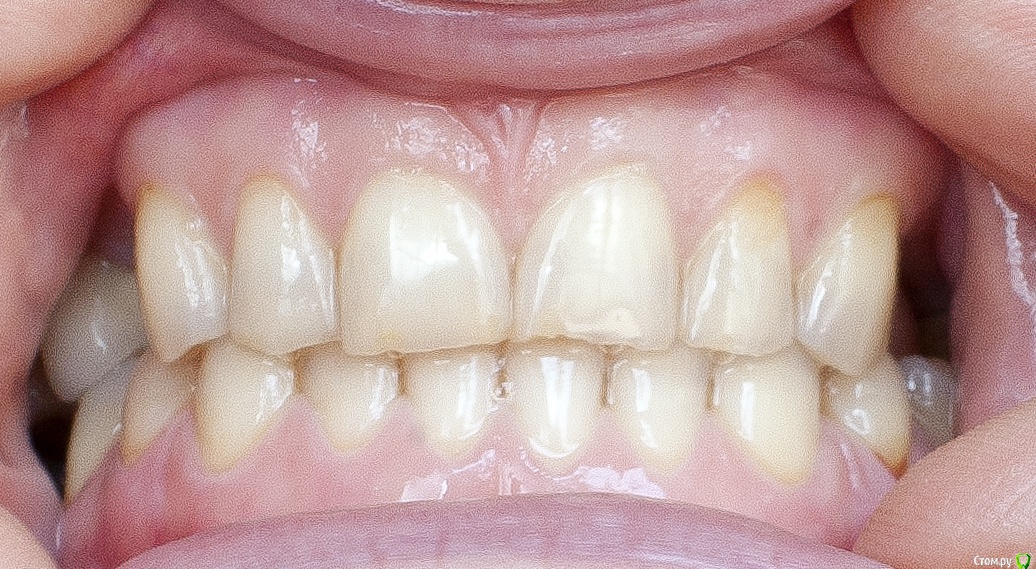

Barbar Опубликовано 16 июля, 2015 Поделиться Опубликовано 16 июля, 2015 Добрый день! У меня неправильный прикус и отсутствуют зубы 14, 24, 25, 36, 37, 46, которые я в ближайшее время собираюсь заменить имплантами. Мне 43 года.Подскажите, пожалуйста, с чего начать: с имлантов или исправления прикуса? Возможно ли решить проблему прикуса брикетными системами? можно ли исправить лингвальными брикетами? применить на обе челюсти?Или есть другое решение?Огромное спасибо за рекомендации заранее! Ссылка на комментарий

Barbar Опубликовано 21 июля, 2015 Автор Поделиться Опубликовано 21 июля, 2015 что именно Вам мешает широко улыбаться??? форма зубов, их расположение, отсутствие боковых зубов...? что именно Вы хотели справить с помощью брекетов? Вам стоматолог посоветовал заниматься прикусом или это Ваши предположения? если хотите просто поставить отсутствующие зубы - то Вам к ортопеду надо. Он посмотрит и скажет , ДОСТАТОЧНО ли места по ширине и высоте для имплантации и протезирования. если да, то просто протезируйтесь. Если же нет - то тогда Вам к ОРТОДОНТУ. Да, да и да! " форма зубов, их расположение, отсутствие боковых зубов..."Ладно, их расположение устраивает, во рту они как раз на правильном месте %РМне не нравится, что зубы пожелтели, неровны и сточены, особенно нижние. И прикус!Верхние зубы направлены немного вовнутрь и перекрывают нижние, у которых от этого сильный наклон вовнутрь. Уж не знаю как лучше объяснить, я не врач и терминами не владею. Думала, что всё понятно по фото. Улыбка получается жалкая. Имплантаты на место отсутствующих зубов будут ставить, уже решено. 6 штук, что недёшево. Но хотелось наконец решить эту проблему так, чтобы не было мучительно... то есть все продумать и закрыть тему зубов на долгие годы. Исправить прикус тоже.Мои вопросы были - с чего начать? Какие варианты? Помогут ли (для прикуса) просто коронки на передние нижние зубы? тогда придётся закрыть коронками весь ряд? или только 6 зубов? Или поставить имплантаты и постепенно исправлять прикус лигвальными брикетами? Но тогда высота имплантатов после исправления будет недостаточной? Ссылка на комментарий

Barbar Опубликовано 23 июля, 2015 Автор Поделиться Опубликовано 23 июля, 2015 И причём безо всяких брикетов. По сценарию: пришла, заснула, очнулась - мне зубы, а ему деньги. Я думаю, это мечта любого стоматолога (прошу не обижаться, это добрая шутка)По поводу эстетики - вам правда мои зубы кажутся в полном порядке или просто у вас мои фото в полный размер не открываются? На последней фотографии особенно видно, что нижние зубы сточены и пожелтели, а верхние неровные, имеют зазубренные края и частично уже прозрачные, или нет? Вы, как стоматолог, можете видеть проблемы в зубах, кажущихся идеальными, что простым смертным не под силу, и при этом мои зубы Вам кажутся вполне эстетичными? Ссылка на комментарий

Yana guapa Опубликовано 23 июля, 2015 Поделиться Опубликовано 23 июля, 2015 По поводу эстетики - вам правда мои зубы кажутся в полном порядке или просто у вас мои фото в полный размер не открываются? На последней фотографии особенно видно, что нижние зубы сточены и пожелтели, а верхние неровные, имеют зазубренные края и частично уже прозрачные, или нет? Вы, как стоматолог, можете видеть проблемы в зубах, кажущихся идеальными, что простым смертным не под силу, и при этом мои зубы Вам кажутся вполне эстетичными?многие пациенты позавидовали бы Вашим зубам )) пусть и боковые Вы по каким то причинам потеряли , но передние зубы здоровые.немного стерлись режущие края (но вы не забывайте что и со временем у всех людей стираются зубы, ну и конечно Вы их повышенно истирали в связи с отсутствием боковых зубов). их можно заполировать просто. Я так понимаю что все-таки Вас больше беспокоит непосредственно расположение зубов, степень их обнажения при улыбке - это тогда исправлять только брекетами. Вообще - улыбку нужно уметь носить и преподносить!)) Возможно можно ее дополнительно оформить, например, сделать губы немного пухлее, тогда вся улыбка станет выразительнее. как вариант - подумайте) Ссылка на комментарий